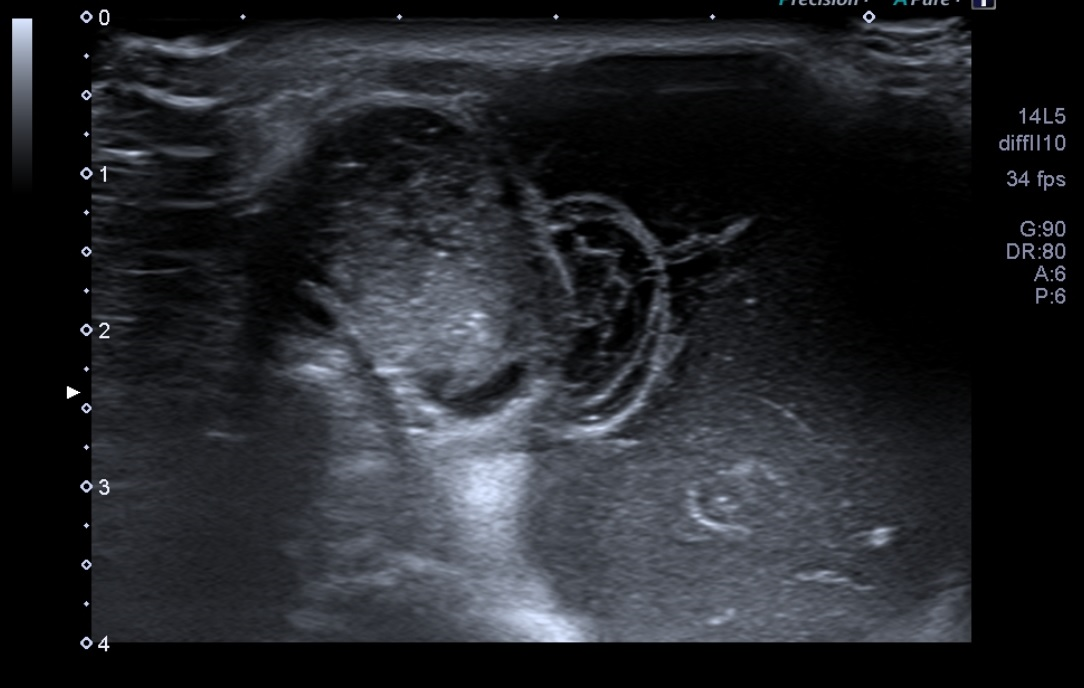

Ante la sospecha de quiste sinovial se realiza Ecografía músculo esquelética en consulta.

Hallazgos ecográficos

Difícil acceso por las forma de la masa. Se observa en plano dérmico lesión sin pared de 1,85 cm en su mayor altura, aneicoica con flóculos en su interior. No parece depender de la articulación del hombro ni la acromionclavicular, no se aportan más medidas por salirse de la ventana del ecógrafo.